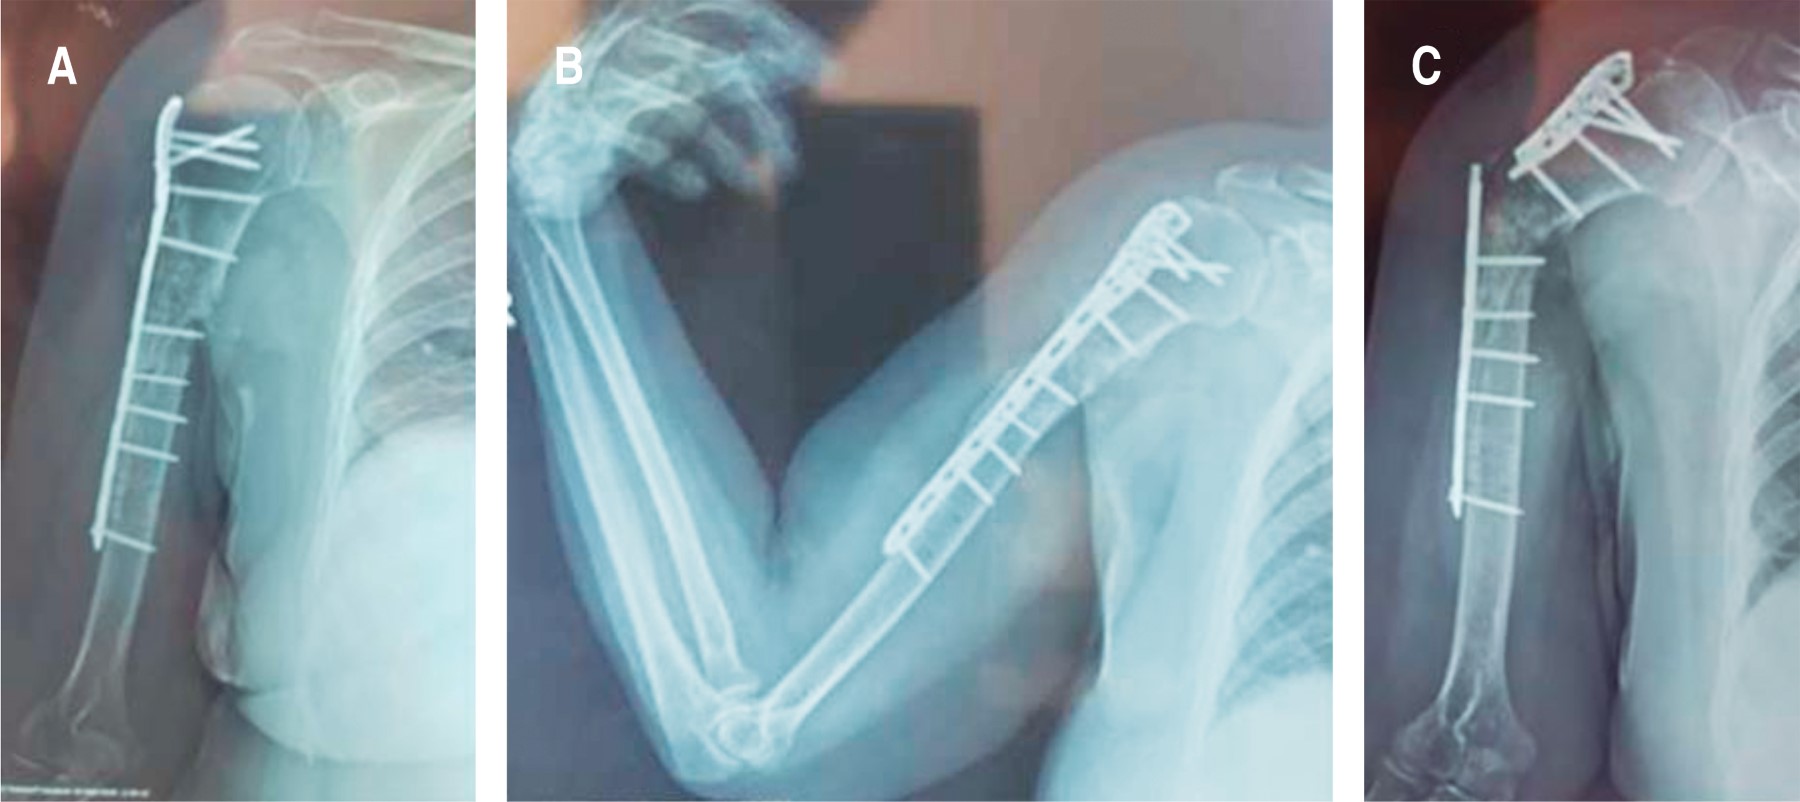

Introduction: different techniques have been described for the treatment of nonunion. However, there are very few reports on the use of autologous tricortical iliac crest graft. The objective of reporting this case is to emphasize the importance of using the autologous tricortical iliac crest graft, in the context of the "diamond concept", after 3 failed surgeries for humerus nonunion. Case report: female, 69 years old, type 2 diabetes mellitus, grade III obesity, diagnosis of aseptic oligotrophic nonunion of the right humerus plus radial nerve injury, underwent 3 previous surgeries without success in resolution. The treatment consisted of performing osteosynthesis with an locking compression plate (LCP) for the proximal humerus and application of the "diamond concept" through the use of autologous tricortical iliac crest graft, bone marrow aspirate, platelet-rich plasma and demineralized bone matrix, as well as exploration and decompression of the radial nerve, achieving complete consolidation and functional recovery. Conclusion: after 3 failed surgeries, and after a bone loss of 7 cm, complete bone consolidation and full functional recovery are achieved through the application of the "diamond concept" with the complement of the use of autologous tricortical iliac crest graft.

Figure 3